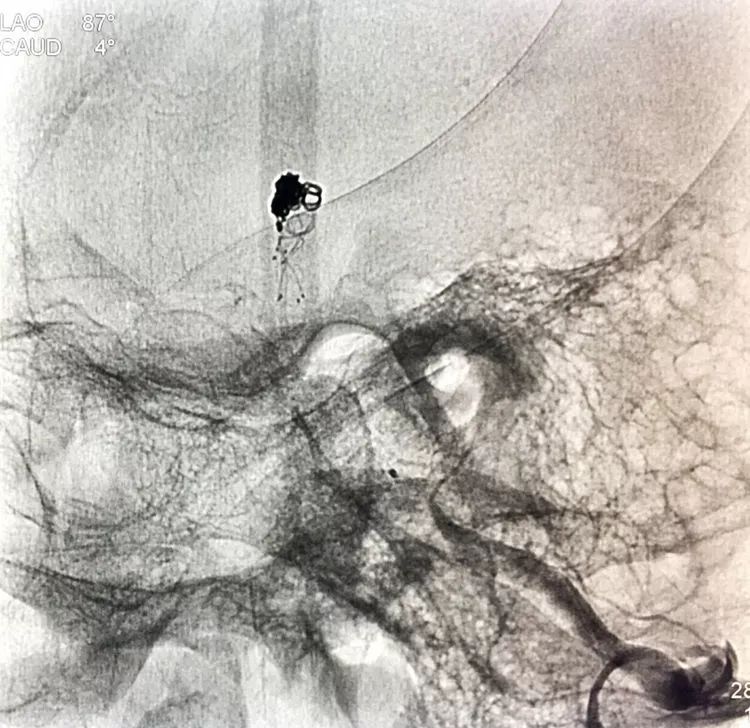

左椎动脉工作位路图

将LVIS支架(3.5×15)跨瘤颈释放于右侧PCA-基底动脉内

在支架保护下输送弹簧圈栓塞瘤腔

此时从工作位(右斜17°反汤9°)看弹簧圈分布致密,微导管头已被顶到瘤颈处

工作位造影看动脉瘤栓塞满意,子瘤已不显影,是不是可以收手了呢?

旋转增强器透视观察各个投照角度弹簧圈的分布情况,侧位透视发现瘤腔后部的弹簧圈分布疏松,形成死腔,看来革命还未成功,同志尚需努力呀!